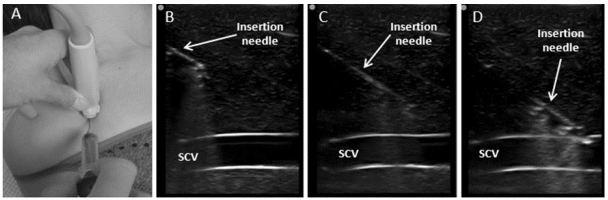

Despite multiple advantages, subclavian vein (SCV) cannulation via the traditional landmark approach has become less used in comparison to ultrasound (US) guided internal jugular catheterization due to a higher rate of mechanical complications. A growing body of evidence indicates that SCV catheterization with real-time US guidance can be accomplished safely and efficiently. While several cannulation approaches with real-time US guidance have been described, available literature suggests that the infraclavicular, longitudinal "in-plane" technique may be preferred. This approach allows for direct visualization of needle advancement, which reduces risk of complications and improves successful placement. Infraclavicular SCV cannulation requires simultaneous use of US during needle advancement, but for an inexperienced operator, it is more easily learned compared to the traditional landmark approach. In this article, we review the evidence supporting the use of US guidance for SCV catheterization and discuss technical aspects of the procedure itself.

尽管有多种优势,但与超声引导下的颈内静脉置管相比,经传统体表标志法进行锁骨下静脉(SCV)置管因机械并发症发生率较高而较少使用。越来越多的证据表明,在实时超声引导下进行SCV置管可以安全、有效地完成。虽然已经描述了几种实时超声引导下的置管方法,但现有文献表明,锁骨下、纵向“平面内”技术可能更受青睐。这种方法可以直接观察到穿刺针的推进,从而降低并发症风险并提高置管成功率。锁骨下SCV置管在穿刺针推进过程中需要同时使用超声,但对于经验不足的操作者来说,与传统体表标志法相比,它更容易掌握。在本文中,我们回顾了支持超声引导下进行SCV置管的证据,并讨论了该操作本身的技术要点。